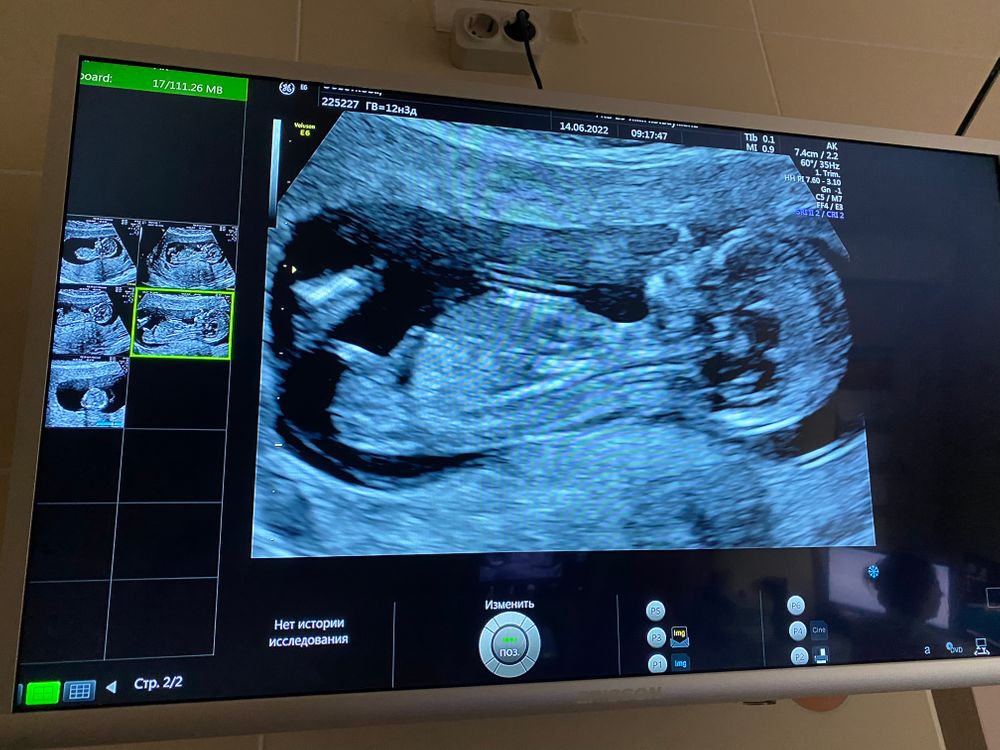

Настенька мамочка сыночков и ,  Изображение Вот ещё фото

Досего хороший пупсов лежит😀но я не разбираюсь еще

Мими, поймали в танце😄узист сказала непоседа)